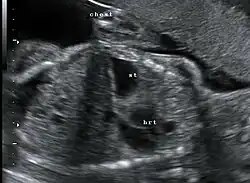

Congenital diaphragmatic hernia: coronal obstetric ultrasound (head to right of image, thorax centre, abdomen left) shows the stomach and heart both within the thorax.

This condition can often be diagnosed before birth and fetal intervention can sometimes help, depending on the severity of the condition.[8] Infants born with diaphragmatic hernia experience respiratory failure due to both pulmonary hypertension and pulmonary hypoplasia. The first condition is a restriction of blood flow through the lungs thought to be caused by defects in the lung. Pulmonary hypoplasia or decreased lung volume is directly related to the abdominal organs presence in the chest cavity which causes the lungs to be severely undersized, especially on the side of the hernia.

Survival rates for infants with this condition vary, but have generally been increasing through advances in neonatal medicine. Work has been done to correlate survival rates to ultrasound measurements of the lung volume as compared to the baby's head circumference. This figure known as the lung-to-head ratio (LHR). Still, LHR remains an inconsistent measure of survival. Outcomes of CDH are largely dependent on the severity of the defect and the appropriate timing of treatment.